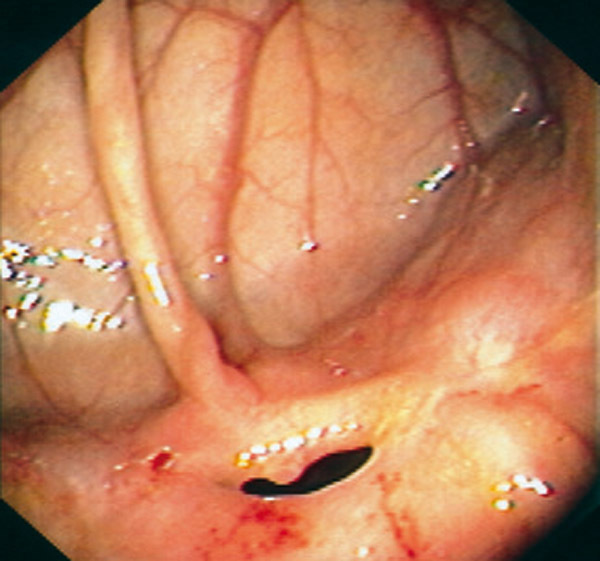

Maladie de Crohn : aspects endoscopique

Sténose non ulcérée.